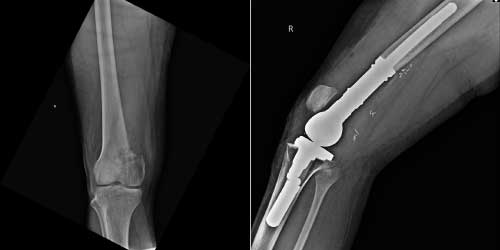

Tedavide başarıyı artıran en önemli etkenlerden biri ameliyat öncesi iyi bir hazırlık ve cerrahi planlama yapmaktır. Her şeyden önce tanı doğru konmalı. Bunun için hasta iyi dinlenip, detaylı muayene edildikten sonra tetkikleri dikkatli incelenmelidir.

Her ameliyatın olduğu gibi kemik ve yumuşak doku tümör ameliyatlarının da riskleri vardır. Bu riskleri genel ve yapılan ameliyata özgü olmak üzere kabaca iki başlık halinde gruplandırabiliriz. Öncelikle anestezi ile ilgili risklerin anestezi uzmanı tarafından (...)

Ameliyat sonrası takip ve kontrol hastanın ameliyat masasında uyanması ile başlar. Özellikle damar ve veya siniri ilgilendiren ameliyatlarda hasta ameliyat masasından alınmadan ekstremitenin dolaşımı ve ilgili sinirin fonksiyonu kontrol edilir.